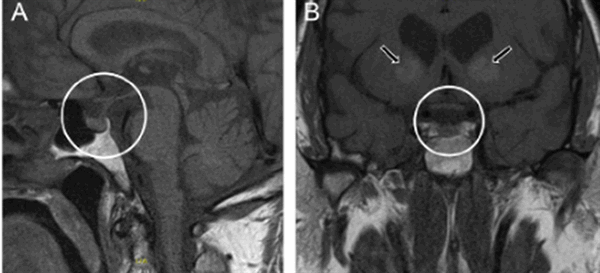

МРТ гипофиза с контрастом и без: А- гипофиз нормальных размеров (обведено кругом), В - симметричные кальцификации (стрелки)

Вопрос что лучше сделать: “МРТ гипофиза с контрастом или без?” - должен решить врач. Последний порекомендует приемлемые для получения качественных изображений характеристики аппарата: сканы, сделанные с помощью низкопольных аппаратах с открытым контуром малоинформативны. Оптимально пройти обследование на томографе с мощностью от 1,5 Тесла.

Учитывая размер гипофиза (с горошину), МРТ преимущественно выполняют с введением контрастного вещества. В качестве красителя используют растворимые соли (хелаты) гадолиния, которые не представляют опасности для организма и при накоплении тканями обеспечивают лучшую визуализацию. Побочные эффекты встречаются менее, чем у 1% людей. Контрастирование ограничивают:

МРТ гипофиза с контрастом в детском возрасте до 12 лет проводят в стенах больницы. Усиленную магнитно-резонансную томографию назначают в рамках предоперационной оценки перед удалением опухоли (в том числе аденомы) или кисты мозгового придатка, для определения характера изменений тканей после вмешательства (позволяет дифференцировать сформировавшийся рубец от рецидива новообразования) и пр. В качестве дополнительного способа проводят еще и КТ, которая лучше демонстрирует изменения, исходящие из костных структур и показывает патологии турецкого седла, кровоизлияния в питуитарную железу. МРТ гипофиза без контраста малоинформативна.